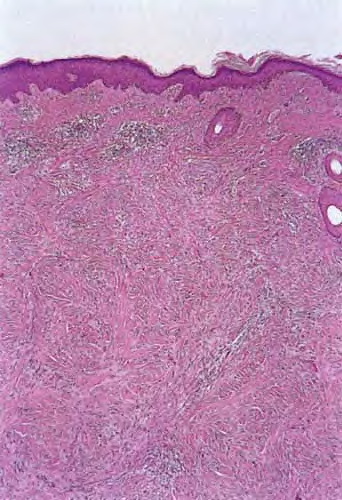

Desmoplastic melanoma = الميلانوم المكون للالتصاقات